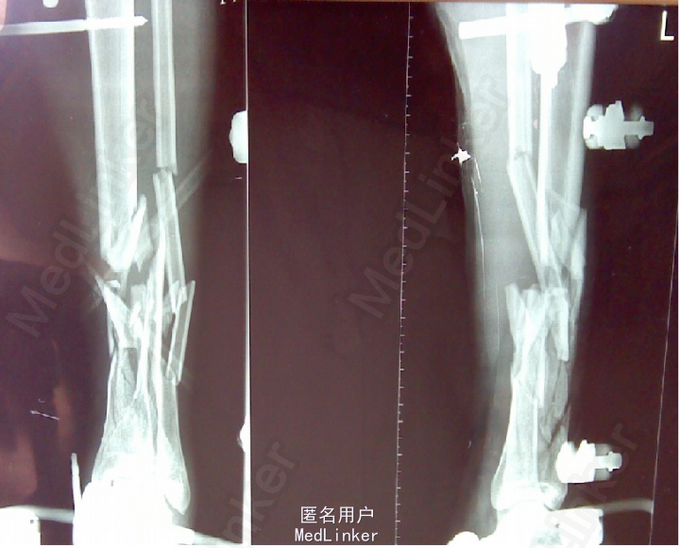

粉碎性骨折x光图片,粉碎性骨折片子图片

粉碎性骨折片子图片

小腿粉碎性骨折图片